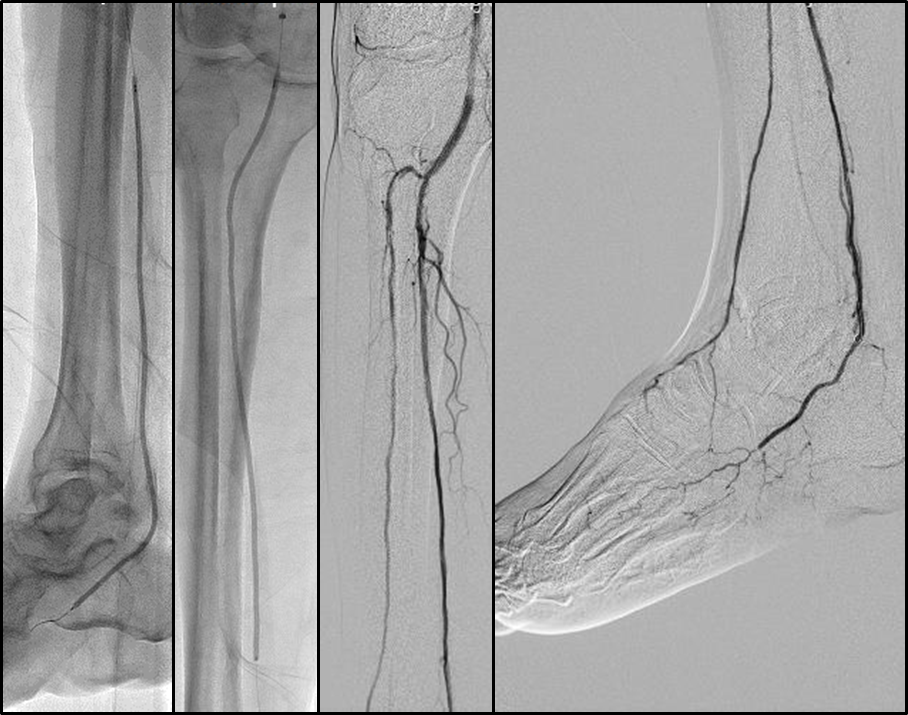

BTK 标准化开通流程

Ante-True Lumen

Fail + short lesion

Fail →Retro puncture

Fail → SAFARI/CART/r-CART

Fail + long lesion

Fail → PA/PTA

Fail → ATA

Fail → PCA

Fail → Puncture

Fail → Pedal arch

Antegrade access with retrograde wireguided

通过深入剖析解剖规律、明确技术选择边界、并提出一套简化的标准化流程,为临床医生处理BTK-CTO病变提供了清晰、实用的操作指南,有助于提高手术成功率,改善CLTI患者的保肢预后。